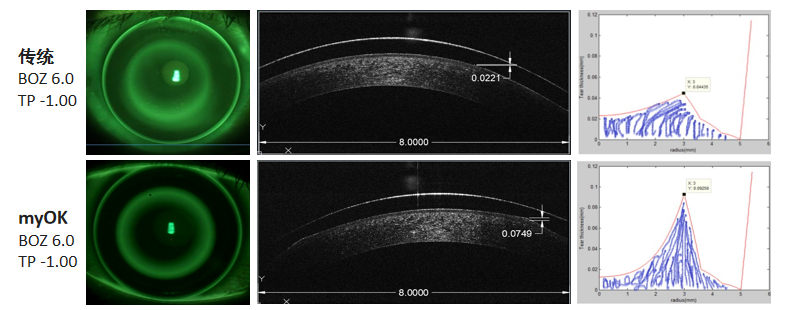

1. 通过前节OCT发现全屏非球面组在角膜前表面产生更高的矢高(变异系数)更大;

2. 通过视网膜周边屈光力的变化,在配戴后视网膜周边离焦由远视化朝近视化漂移,全屏非球面的改变更为显著:

通过以上的研究数据,myOK4.0强效相较于传统设计增加配适稳定性和舒适度,增加周边离焦量,同时保证离焦刺激有效入瞳进而对缓解眼轴增长起到更为有效的控制作用。